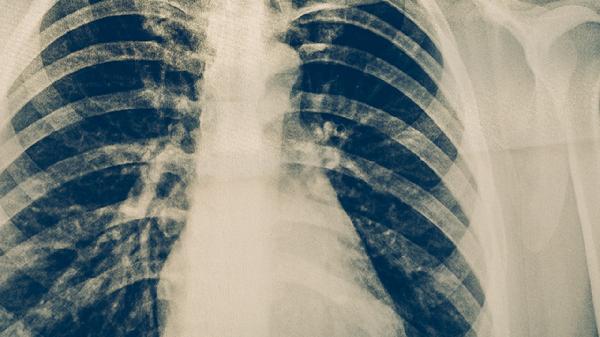

肺部肿瘤的中药治疗需在医生辨证指导下进行,常用方法包括使用具有抗肿瘤作用的中药复方、单味药及辅助调理方剂。主要治疗手段有扶正固本类方剂、活血化瘀类中药、清热解毒类制剂、软坚散结类药材以及辨证施治的个体化方案。中药治疗通常作为手术或放化疗的辅助手段,需严格避免替代规范医疗。

中药治疗需配合影像学复查评估效果,出现咯血、持续发热应立即停用。治疗期间保持饮食清淡,适量食用百合、银耳等润肺食材,避免辛辣刺激食物。所有中药使用前应确认与西药无相互作用,肿瘤进展时须及时转为手术或放疗等主流治疗。